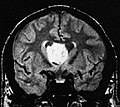

Subependymoma. H&E stain.

Images